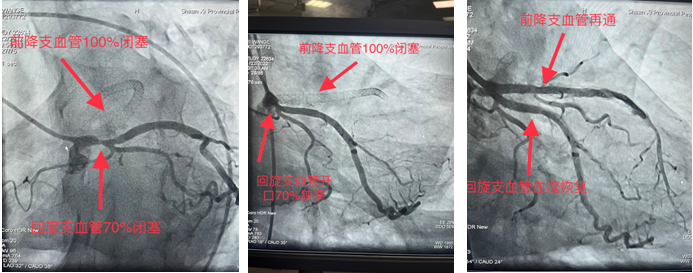

求医,心血管内一科收入,并于11月22日安排冠脉手术为患者诊治病症。造影显示前降支支架内100%闭塞,回旋支开口70%狭窄。由于血管闭塞时间久,且之前支架内完全闭塞,术中出现心律缓慢、血压下降等危险因素。最终,在心血管内一科张勇主任医师、潘硕副主任医师、马彦鹏主治医师及介入放射诊疗手术室护师郭朝望、技师吴华楠等的默契配合和共同努力下,陈旧性冠状动脉闭塞血管得以再通,心脏血流恢复,生命体征随之好转,手术顺利完成。